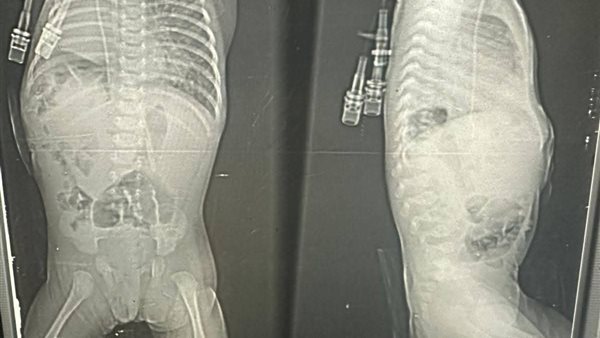

وكانت الرضيعة تعاني من فتق بالحجاب الحاجز من الجهة اليمنى من نوع “بوكدالك مرتد”، مصحوب بانسداد معوي، وصعوبة شديدة في التنفس، إلى جانب التهاب رئوي حاد، وهي حالة شديدة الخطورة استدعت تدخلًا عاجلًا متعدد التخصصات.

وعلى الفور، جرى استقبال الحالة وإيداعها بقسم الأطفال المبتسرين داخل حضانة مجهزة، مع إجراء الفحوصات الطبية والأشعات اللازمة، إلى جانب فحص القلب بالموجات فوق الصوتية، تمهيدًا للتدخل الجراحي.

وخلال العملية، تبيّن وجود التصاقات شديدة بالأمعاء والتواء بالأمعاء والإثني عشر، إضافة إلى فشل الإصلاح الجراحي السابق للفتق. وقام الفريق الطبي بإزالة الخيوط القديمة، وردّ الأمعاء والكلية اليمنى إلى موضعهما الطبيعي داخل التجويف البطني، مع استعدال الأمعاء بطريقة “لادز” الجراحية، واستئصال الزائدة الدودية، ثم إصلاح فتق الحجاب الحاجز بخيوط إيثيبوند وغلق جدار البطن بإحكام.